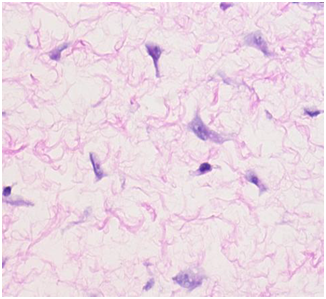

The soft tissue sonogram showed a mass measuring approximately 5.3 cm x 4.7 cm x 2.3 cm, which was projecting from a vascular stalk on the labial majora. The lesion was mildly heterogeneous in echotexture, appearing predominantly solid (Figure 3). The patient underwent wide local excision of the mass. Pathology of the mass showed an aggressive angiomyxoma. The pathologist also noted “this mesenchymal lesion is locally aggressive with a high risk for recurrence if incompletely excised. Although the pedicle margin of resection appears free of the lesional process further clinical concern may warrant conservative excision at the site of lesion attachment”. It was also noted that the mass was hypocellular and composed of stellate cells with an ill-defined cytoplasm distributed through a finely fibrillar and myxoid matrix. The nuclei were bland and mitoses were not present. There were numerous thin and thick walled blood vessels that blended with the surrounding matrix (Figures 5-8).

Figure 7 The tumor cells (Purple circles) are stellate with bland nuclei and in apparent cytoplasm blending with fibrillar and myxoid cells. (H&E stain).